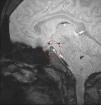

Alteraciones endocrinológicas en un paciente con talasemia mayor

Endocrinological disorders in a patient with thalassemia mayor

Figuras (2)